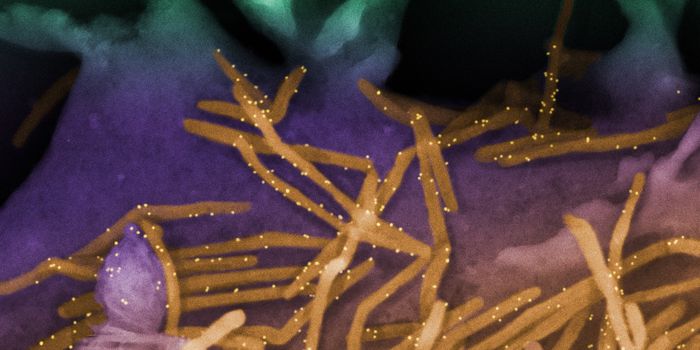

MAR 20, 2024Clinical & Molecular DXA 2020 study called fungal infection a "silent crisis" that was already causing about 1.7 million deaths every year. Dru ...